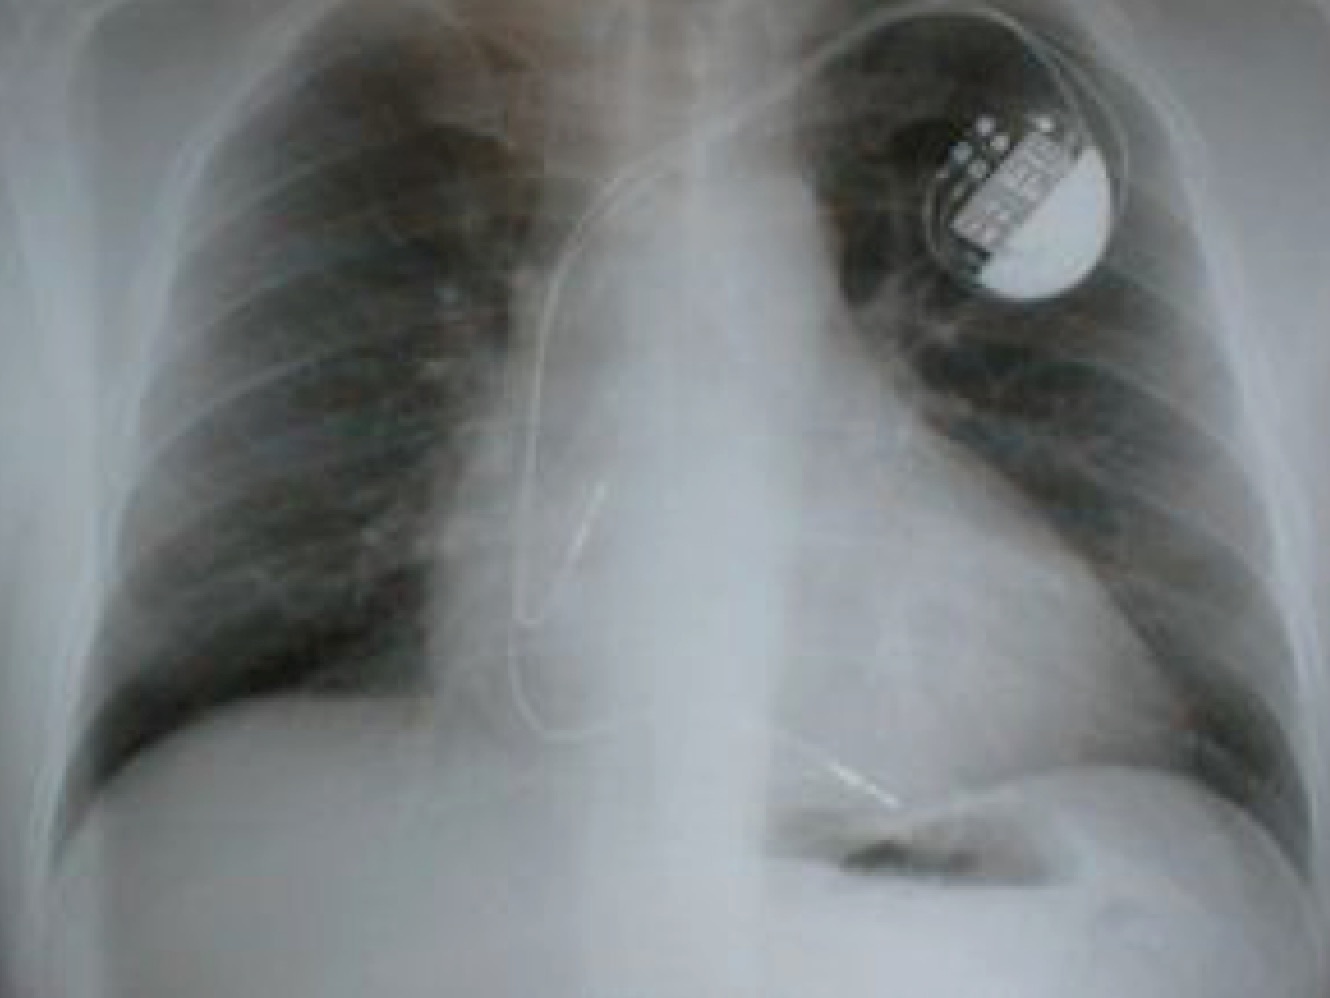

A middle-aged man who had a biventricular pacemaker inserted 3 weeks ago presented with fever as well as pain over the left upper chest wall. Clinical examination revealed erythema and tenderness over the pacemaker body insertion site, with just a small amount of pus expressed from the incision scar. Blood cultures and a swab of the pus from the wound were both positive for methicillin-resistant Staphylococcus aureus with the following drug susceptibility profile (obtained from VITEK2):

This is a particularly difficult type of infection to treat. It is likely that the pacemaker generator/pocket site has been infected, and given the presence of bacteraemia, the infection is unlikely to be superficial/confined to the surgical site alone. A trans-oesophageal echocardiogram (TEE) should be performed to determine if there is any accompanying endocarditis of the heart valves or lead wires, especially given that the bacteraemia and pocket site infection are caused by MRSA. A trans-thoracic echocardiogram – often performed because it is relatively more straightforward a test – lacks sensitivity. The updated American Heart Association recommendations are clear – regardless of whether there is any endocarditis, in this situation, the entire device (including wires and generator) should be removed. Treatment failure is high if the infected foreign body is left in place.